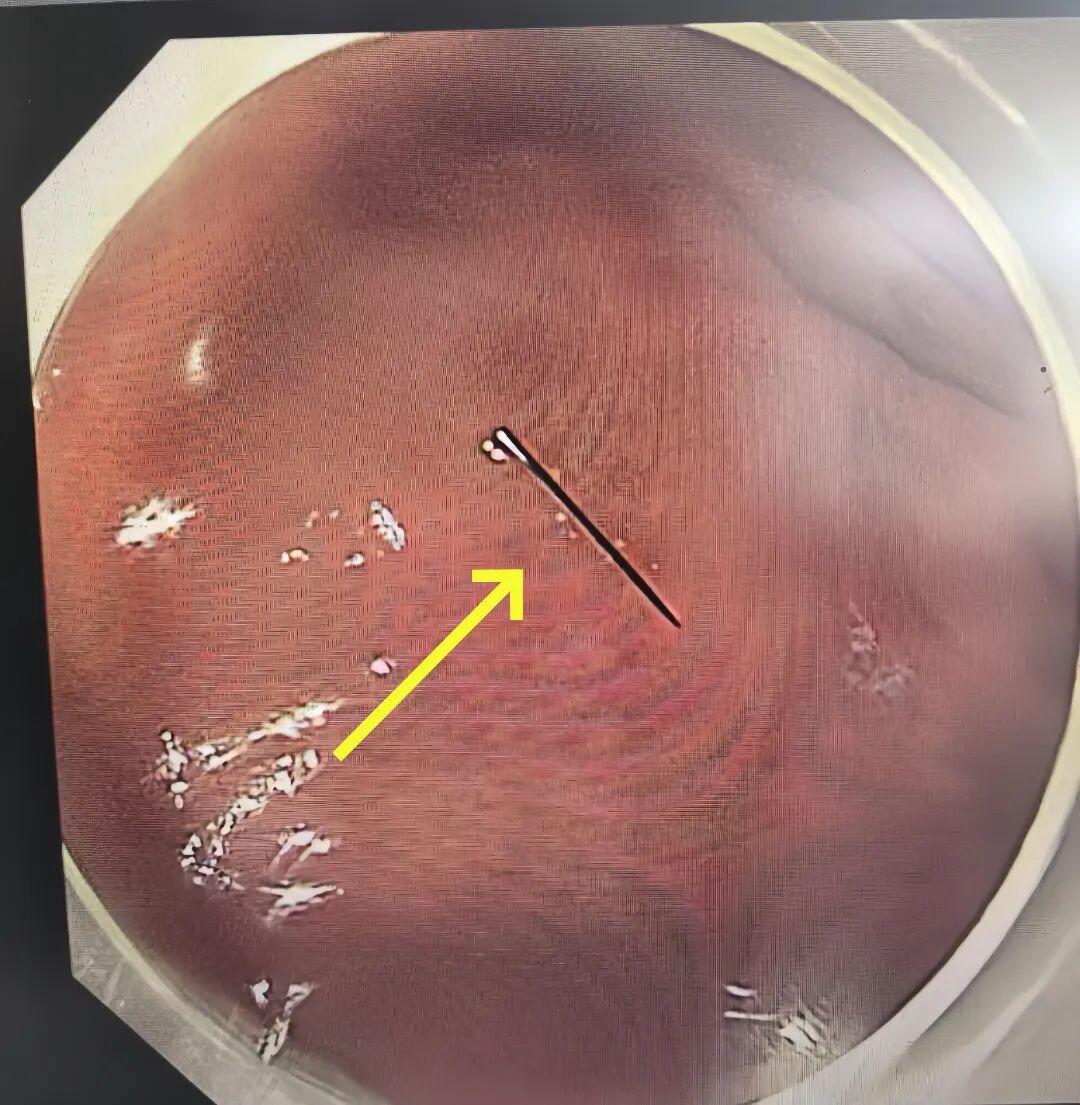

消化内科、内镜中心医护团队立刻响应。大家从家中连夜出发,在最短时间内集结到位。凌晨 3 点,术前准备就绪,一场全麻下胃镜异物取出术正式开始。凭借丰富的儿童内镜经验,手术仅用 10 余分钟就顺利完成,那截约1 厘米长的断针被完整取出。

万幸的是,断针尚未刺破胃黏膜、未造成出血损伤。当医生将取出的断针展示在家人面前时,一直悬着的心终于落地。术后欣欣恢复顺利,状态平稳,目前已康复出院回家。